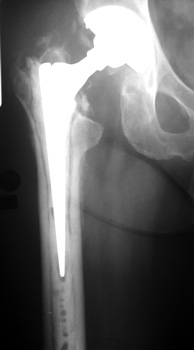

LooseningAs pain and disability due to loosening become severe enough to require revision arthroplasty, abnormalities in the binding of the cement to the bone or prosthesis are almost always visible radiographically. Radiographic abnormalities include:

LOOSENING WITH FEMORAL COMPONENT IN VARUS LOOSENING

No prior studies available. Abnormally widened interfaces surrounding entire cement mantle of femoral component, consistent with loosening.

No prior studies available. Abnormally widened interfaces about femoral component at Gruen zones 1, 6, and 7. Osteolysis at Gruen zone 5 with marked thinning of femoral cortex placing patient at risk for pathologic fracture.